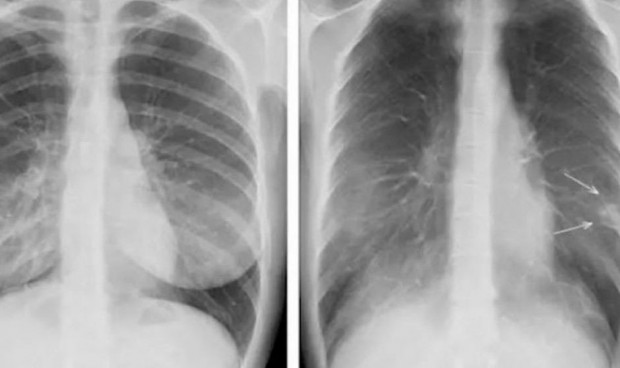

Las fracturas pasadas por alto son una causa común de discrepancia diagnóstica entre la interpretación radiográfica inicial y la lectura final realizada por los radiólogos. Ante esta situación, un grupo de investigadores de la Faculta de Medicina de la Universidad de Boston ha realizado un estudio en el que la inteligencia artificial (IA) puede ayudar a los médicos a detectar fracturas en las radiografías.

"Nuestro algoritmo de IA puede detectar rápida y automáticamente rayos X positivos para fracturas y marcar esos estudios en el sistema para que los radiólogos puedan priorizar su lectura", ha explicado Ali Guermaiz, jefe de Radiología de 'VA Boston Healthcare System' y profesor de Radiología y Medicina en la Facultad de Medicina de la Universidad de Boston (BUSM, por sus siglas en inglés).

En ese sentido, Guermaiz subraya en el estudio que “el sistema también destaca las regiones de interés con cuadros delimitadores alrededor de las áreas donde se sospecha que hay fracturas. Esto puede contribuir potencialmente a reducir el tiempo de espera en el momento de la visita al hospital o la clínica antes de que los pacientes puedan obtener un diagnóstico positivo de fractura".